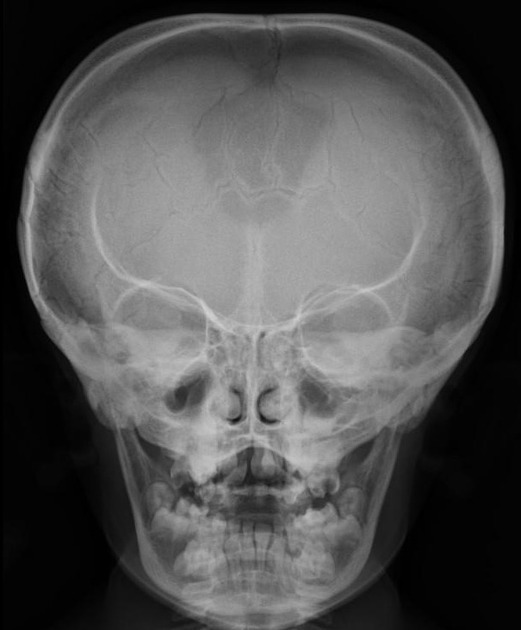

Cleidocranial Dysplasia

AD

Also get wormian bones